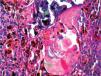

El estudio histopatológico evidenció, en la dermis media y profunda, un tumor pigmentado bien delimitado (fig. 1). Estaba compuesto por una población celular bifásica formada por melanocitos, algunos muy pigmentados, con alguna figura de mitosis, y por otro lado células epiteliales de tamaño variable y citoplasma eosinófilo que de forma abrupta se convertían en células sombra, sin núcleo (fig. 2). Se apreciaban pequeños focos de calcificación (fig. 3).

Su histopatología muestra una proliferación nodular pigmentada en la dermis compuesta por células matriciales, supramatriciales y células sombra mezcladas con abundantes melanocitos dendríticos muy pigmentados. No es frecuente la calcificación ni la reacción granulomatosa1-7.